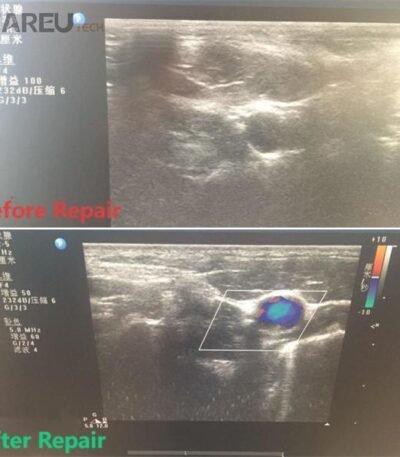

Long-term replacement or good accessory maintenance is necessary to extend the life of your endoscope equipment, and CareU Tech is committed to reducing service costs and minimizing patient risk so that repaired endoscopes always meet optimal performance standards.